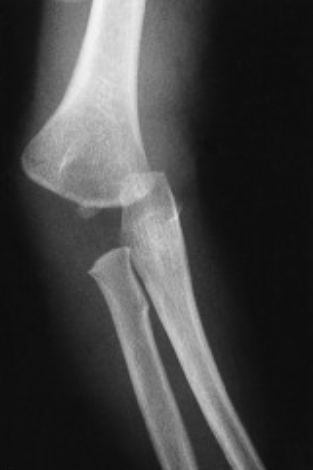

孟氏骨折

儿童孟氏骨折容易漏诊。由于儿童肘部骨骺未完全发育,肱桡关节不匹配容易漏诊,日后未及时随访发现隐匿性孟氏骨折。

孟氏骨折 Bado I 型